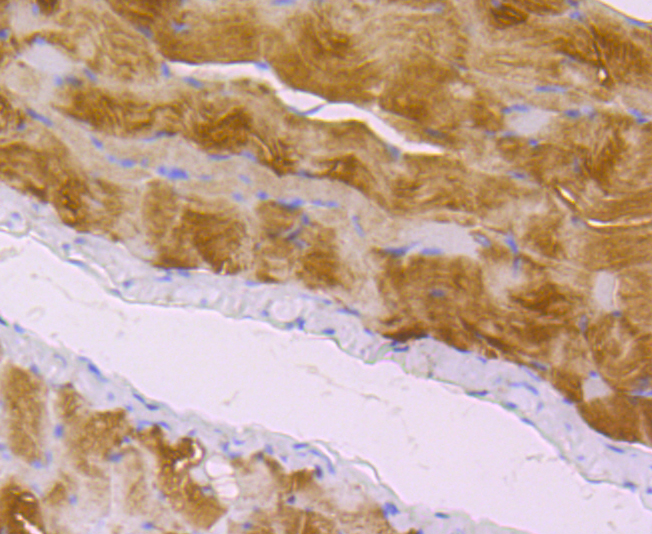

文献和实验:使用 Anti-phospho-Akt (Ser473) Rabbit mAb 对石蜡包埋的人乳腺癌组织进行免疫组织化学分析。(图 A)使用免疫组化试剂盒M&R HRP/DAB Detection IHC Kit,抗体 1:100 稀释;(图 B) 采用普通免疫组化试剂盒,抗体 1:25 稀释。 图 6 免疫组化实验检测 Erk1/2 表达 注:使用 Anti-Erk1/2 Mouse mAb与p44/42 MAPK (Erk1/2)Rabbit mAb 对正常小鼠心脏组织进行免疫